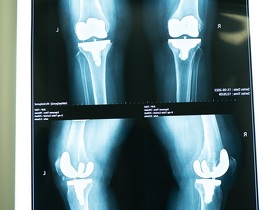

Для постановки диагноза при травматических повреждениях, дегенеративных и воспалительных изменениях в коленном суставе чаще всего используют магнитно-резонансную томографию.

МРТ коленного сустава — это безопасный метод диагностики, при котором отсутствует ионизирующее излучение. Он наиболее точно воспроизводит внутреннюю структуру сустава и патологических состояний, связанных с травмами, с дегенеративными, воспалительными и опухолевыми изменениями.

МРТ коленного сустава в МЕДИКОМ выполняется на современном аппарате экспертного класса. Это лучший способ визуализации любых патологических изменений в суставе, к тому же за наименьшее время врач получает максимальное количество качественных изображений для обработки.